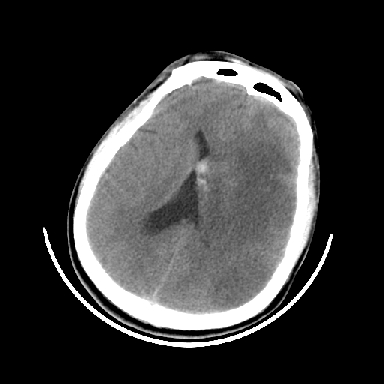

以下是引用dyqct在2007-4-9 11:18:00的发言:[br]左额颞顶叶、基底节区呈大片低密度区,累及皮质,中度占位效应,同侧侧脑室旁见小片状高密度区,边界清楚。中线结构向右弧形移位。右侧侧脑室略扩张。[br]考虑:1、左侧额颞顶叶、基底节区缺血性脑梗塞(符合大脑中动脉供血区)伴出血。[br] 2、建议增强扫描进一步检查。

以下是引用卜一在2007-4-9 15:08:00的发言:[br][br] 左侧额颞顶叶、基底节区缺血性脑梗塞(符合大脑中动脉供血区)伴出血。原因:多考虑外伤后出血,形成血栓所致。 [br]